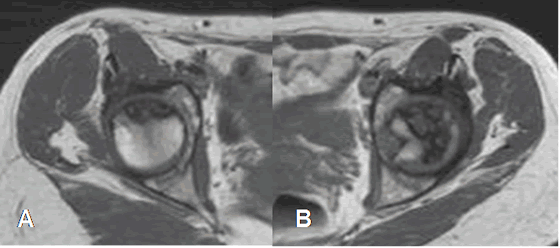

Fig 81. Osteonecrosis.

A: RM axial en T1 y B: RM axial en STIR. Edema óseo inespecífico en la cabeza femoral derecha, hipointenso en T1 e hiperintenso en STIR. Hay escaso derrame asociado.